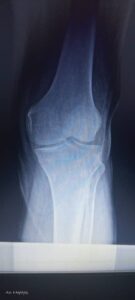

محمي: Knee Surgery جراحة الركبة